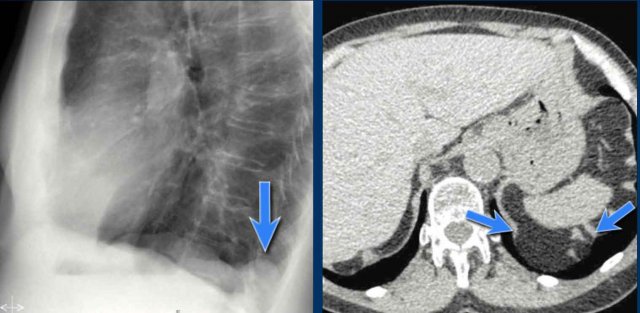

Displacement of the Azygoesophageal Line (1) – Hiatal hernia

A hiatal hernia (arrowheads) is the most common cause of displacement of the azygoesophageal line as seen on the PA-view.

Notice the air within the hernia on the lateral view (black arrow).

Displacement of the Azygoesophageal Line (2) – Subcarinal Lymphadenopathy

A common cause of displacement of the azygoesophageal line is subcarinal lymphadenopathy (station 7).

On the chest X-ray, note superior displacement of the azygoesophageal line just below the carina, consistent with enlarged subcarinal lymph nodes (black arrow).

Additional right paratracheal lymphadenopathy is seen, displacing the right paratracheal stripe (white arrow) and deviating the trachea to the left.